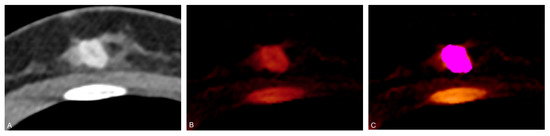

- Zhang, X.; Zheng, C.; Yang, Z.; Cheng, Z.; Deng, H.; Chen, M.; Duan, X.; Mao, J.; Shen, J. Axillary Sentinel Lymph Nodes in Breast Cancer: Quantitative Evaluation at Dual-Energy CT. Radiology 2018, 289, 337–346. [Google Scholar] [CrossRef]

- Zhou, Y.; Su, G.Y.; Hu, H.; Ge, Y.Q.; Si, Y.; Shen, M.P.; Xu, X.Q.; Wu, F.Y. Radiomics analysis of dual-energy CT-derived iodine maps for diagnosing metastatic cervical lymph nodes in patients with papillary thyroid cancer. Eur. Radiol. 2020, 30, 6251–6262. [Google Scholar] [CrossRef] [PubMed]